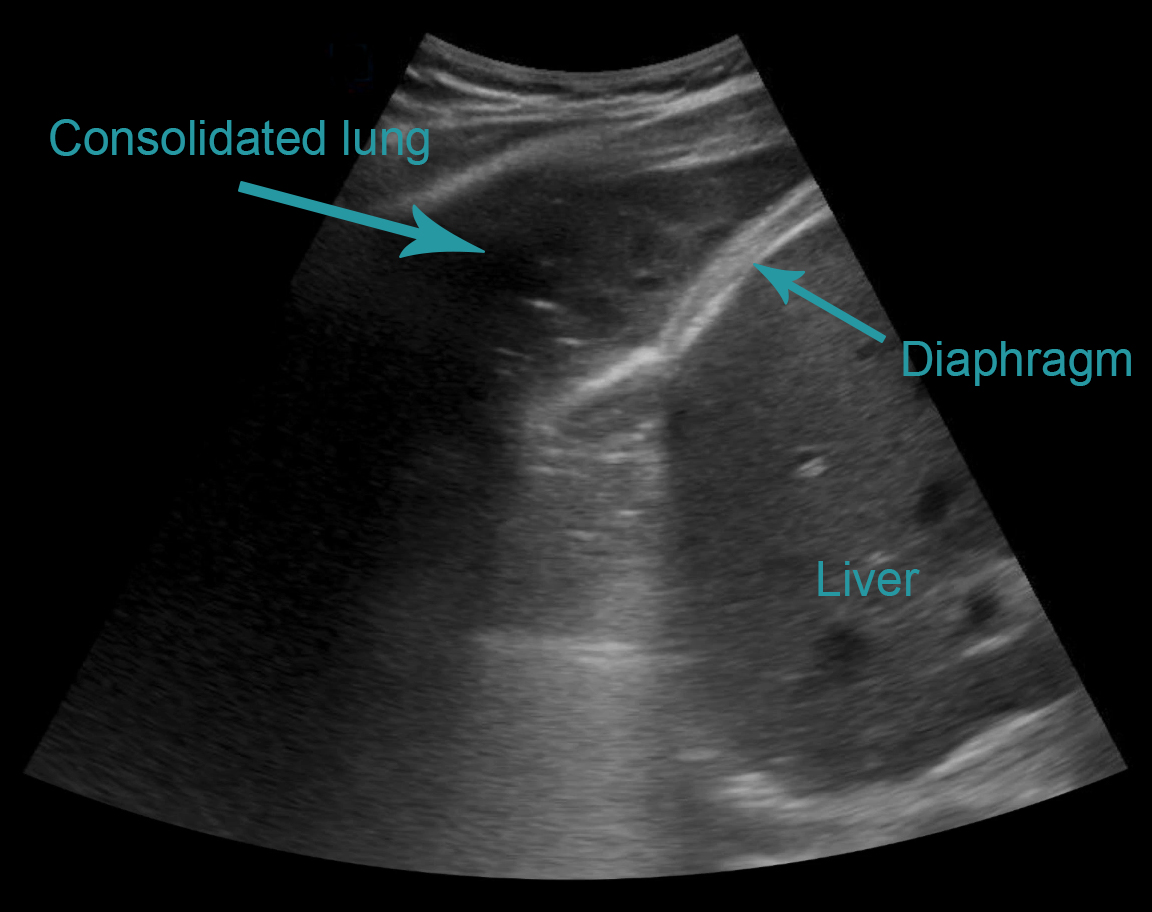

Consolidated lung

Also referred to as ‘lung hepatisation,’ because the lung appears similar to the liver. The alveoli become filled with fluid, allowing the ultrasound energy to pass through without excessive scattering and loss, and return to the probe and create an image.